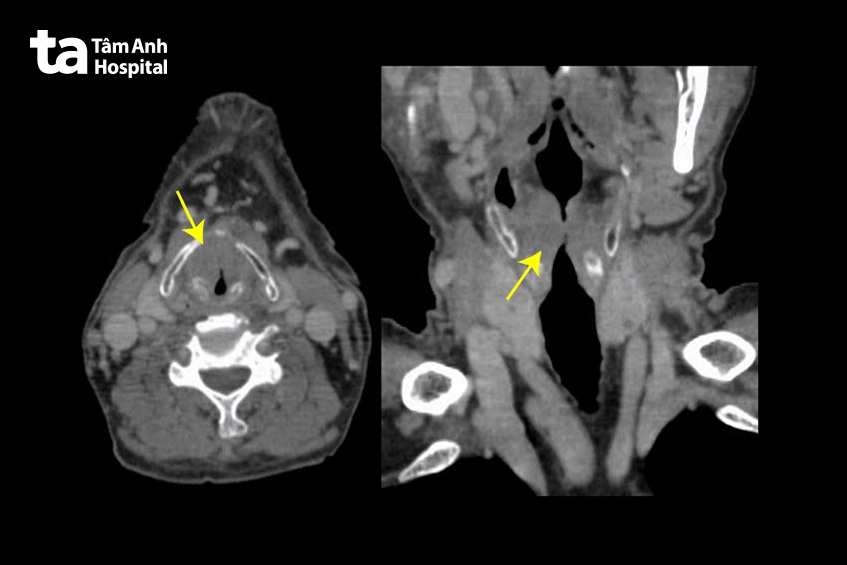

Hình ảnh nội soi tại phòng khám cho thấy u sùi thanh quản nghi ung thư, tuy nhiên không thể quan sát toàn bộ vùng thanh quản do người bệnh khó thở và hạn chế về tư thế ngồi khi khám. Để đánh giá mức độ xâm lấn và sinh thiết khẳng định tính chất khối u, ông Dương cần mở lỗ thông khí quản và nội soi nhằm quan sát toàn bộ khối u vùng thanh quản – hạ họng. Các bác sĩ cẩn thận chỉ định ông Dương khám chuyên khoa Hô hấp, Tim mạch, Gây mê nhằm kiểm tra điều kiện sức khỏe và lựa chọn phương pháp gây mê, đảm bảo an toàn phẫu thuật cho người bệnh cao tuổi.

PGS.TS.BS Lê Minh Kỳ – Phụ trách chuyên môn khoa Tai Mũi Họng, Bệnh viện Đa khoa Tâm Anh Hà Nội, trực tiếp thực hiện mở khí quản và nội soi thăm dò tình trạng bệnh. Kết quả nội soi thanh quản hạ họng cho thấy u sủi toàn bộ thanh quản trái, lan tới mép dây thanh. Kết quả sinh thiết sau đó khẳng định toàn bộ các mẫu bệnh phẩm lấy từ thanh quản là ung thư biểu mô tế bào vảy.